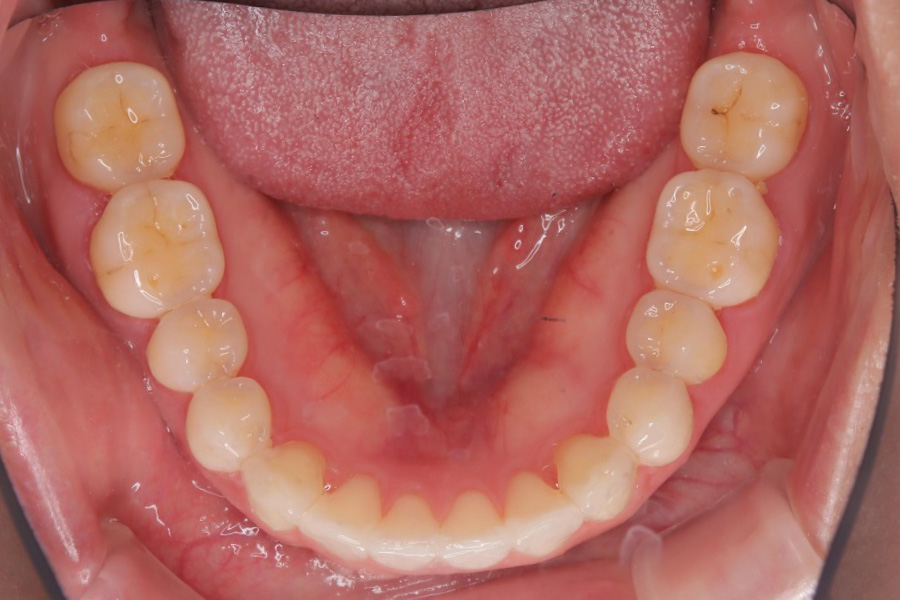

【20代女性】

歯のガタつきを

インビザライン矯正で治療したケース

治療前

主訴 ガタつき

期間 2年

費用 220,000円〜660,000円

治療内容 インビザライン矯正

非抜歯